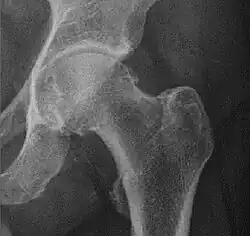

![Normal hip.[3]](./_assets_/X-ray_of_measurements_on_a_normal_hip.jpg)